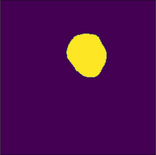

Figure 6 illustrates the segmentation outcomes attained with different neural networks using the same dataset. The enhanced U-Net network proposed in this study is evaluated alongside expert gold standards, Swin-Unet, U-Net, and other well-known network models. The segmentation results from the Swin-Unet network show jagged edges and less smooth nodule edge segmentation, leading to suboptimal outcomes. In the case of U-Net, there are evident under-segmentations with significant discrepancies in the segmented area of some nodules, resulting in inaccurate segmentation results. However, the use of the improved U-Net network introduced in this research produces smoother edges of the segmented thyroid nodules, and the edge contours more closely align with those of the expert gold standard. Moreover, the errors in shape and segmented area are smaller compared to those seen with U-Net and Swin-Unet. The findings suggest that the improved U-Net network provides superior performance in thyroid nodule segmentation.

Draft Xu 795668614-image18.png

(e) Segmentation results after the improvements in this study

Figure 6. Ultrasound image segmentation results of thyroid nodules using different networks